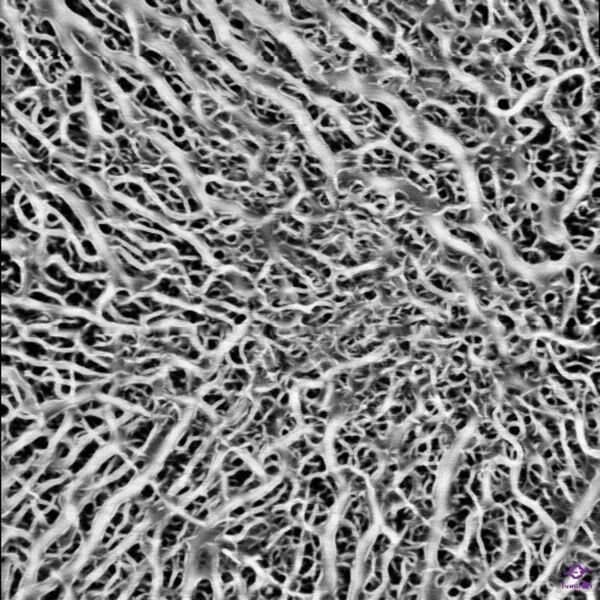

-His main specialties are medical retina (AMD, maculopathies), and ophthalmic surgery (retina and cataract).

-Le Professeur Eric SOUIED has contributed to more than 600 scientific publications in the field of AMD, hereditary retinal diseases, and multimodal imaging. In 1998, he identified the first genetic polymorphism associated with AMD. He is also a member of the Macula Society, Jules Gonin Club, Donald Gass Club, IntRIS, the American Academy of Ophthalmology, ARVO, Euretina, and the National Academy of Surgery. He received the 2017 Macula Society Award